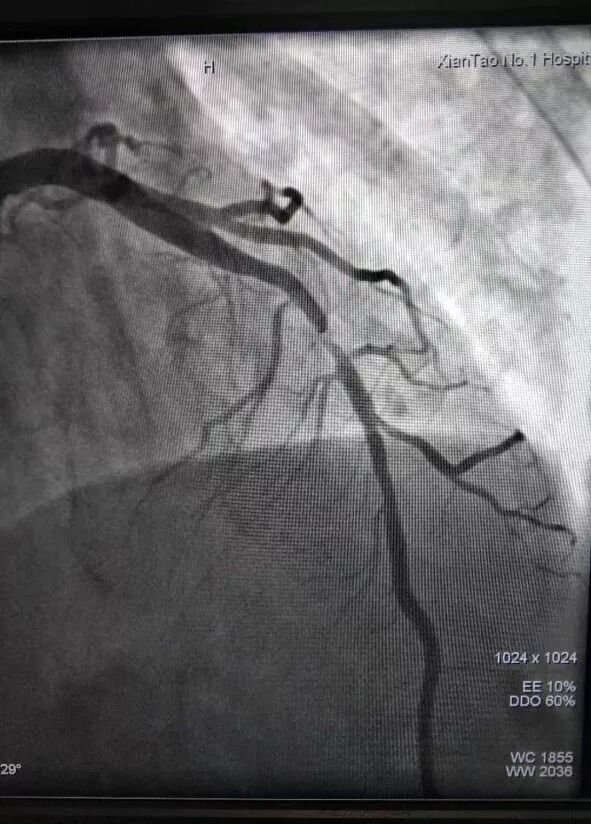

前降支中段植入支架后影像

患者达到心血管内科病房,复查心电图后,立即给予抗血小板、调脂、溶栓等治疗缓解症状。随后,进行介入手术。冠脉造影提示前降支中段有血栓,导致血管近乎闭塞,经过40分钟的手术,成功植入支架一枚,复查造影提示支架形态良好,血管畅通,患者转危为安。